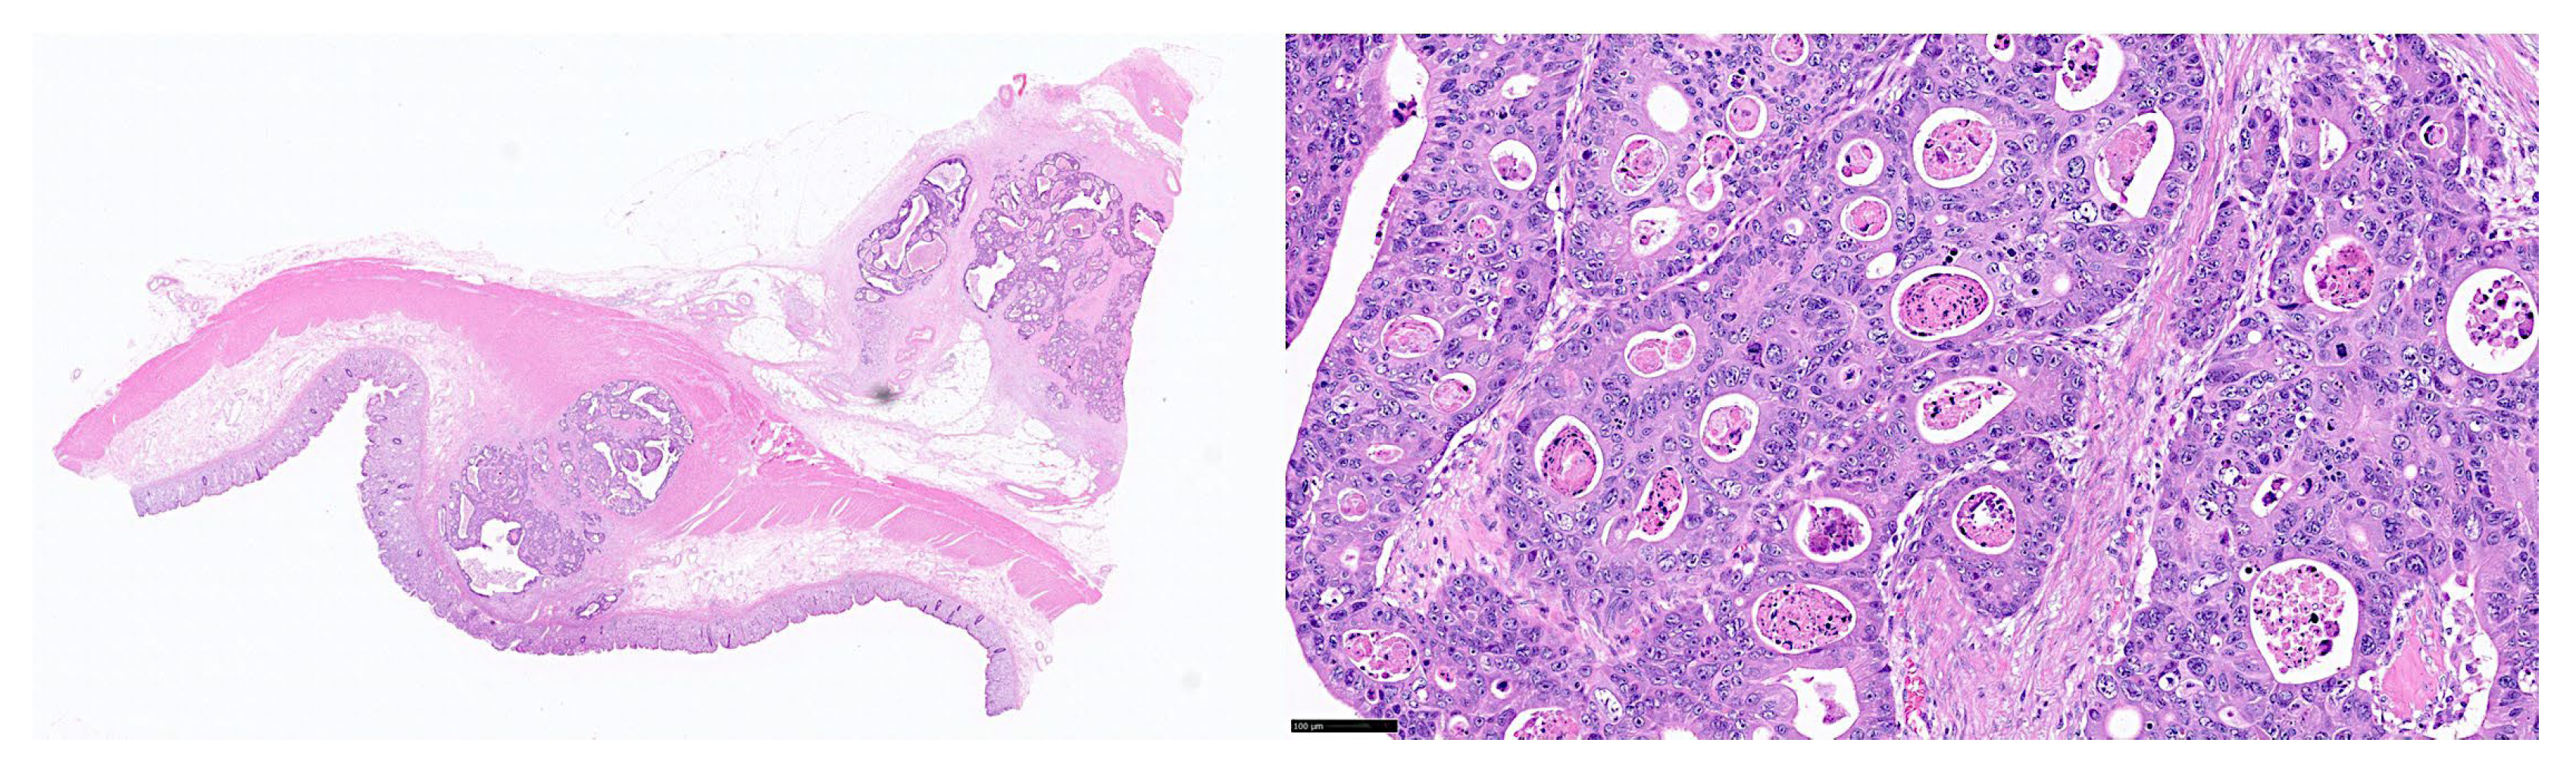

2. Data Description

5. Discussion